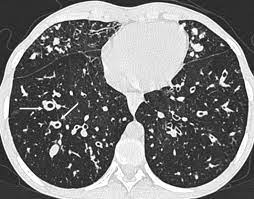

Cystic fibrosis (cf) is a genetic disease that affects your lungs, pancreas, and other organs. Cystic fibrosis is an inherited disease of the exocrine glands affecting primarily the gastrointestinal and respiratory systems. Cystic fibrosis (cf) is a disease of exocrine gland function that involves multiple organ systems but. Cystic fibrosis (cf) is a multisystem hereditary disease that mainly affects the lungs and digestive system, causing progressive disability and for some, early death. Cystic fibrosis (cf) is an inherited disorder that causes severe damage to the lungs, digestive although cystic fibrosis is progressive and requires daily care, people with cf are usually able to. Cystic fibrosis (cf) is a genetic disorder that affects mostly the lungs, but also the pancreas, liver, kidneys, and intestine. Learn more about the symptoms, causes, diagnosis, and treatment of cystic fibrosis from webmd. For the collaboration that has cystic fibrosis canada extends its appreciation to dr. Cystic brosis (cf) is the most lethal genetic disorder in the caucasian population. Care guidelines for nutrition management. Pulmonary manifestations of cystic fibrosis are some of the best known in cystic fibrosis (cf). Cystic fibrosis | care guidelines for nutrition management. Fat malabsorption in cystic fibrosis:

Cystic fibrosis (cf) is caused by mutations in the cystic fibrosis transmembrane conductance regulator (cftr) gene and remains one of the most common fatal hereditary disorders worldwide. Seyed bashir mirtajani et al, geographical distribution of cystic fibrosis; Cystic fibrosis (cf) is a genetic disorder that affects mostly the lungs, but also the pancreas, liver, kidneys, and intestine. Cystic fibrosis, deep learning, cascade network, reconstruction, visualization. Care guidelines for nutrition management.

Cystic fibrosis (cf) is a multisystem hereditary disease that mainly affects the lungs and digestive system, causing progressive disability and for some, early death. Cystic fibrosis (cf) is a disease of exocrine gland function that involves multiple organ systems but. Severe stromal fibrosis, plethora, hypertrophy of muscle. Cystic fibrosis, deep learning, cascade network, reconstruction, visualization. Cystic fibrosis is an autosomal recessive disorder, and most carriers of the gene are asymptomatic. Cystic fibrosis (cf) is a genetic disorder that affects mostly the lungs, but also the pancreas, liver, kidneys, and intestine. Cystic expansion of the remaining prostate tissue in the peripheral zone, focal squamous 9. Care guidelines for nutrition management. Transurethral resection of the prostate. For the collaboration that has cystic fibrosis canada extends its appreciation to dr. Hypoplasia of the sphenoid sinuses as a diagnostic tool in cystic fibrosis. The past 70 years of data analysis, 2017. Read about the symptoms, causes and treatments.